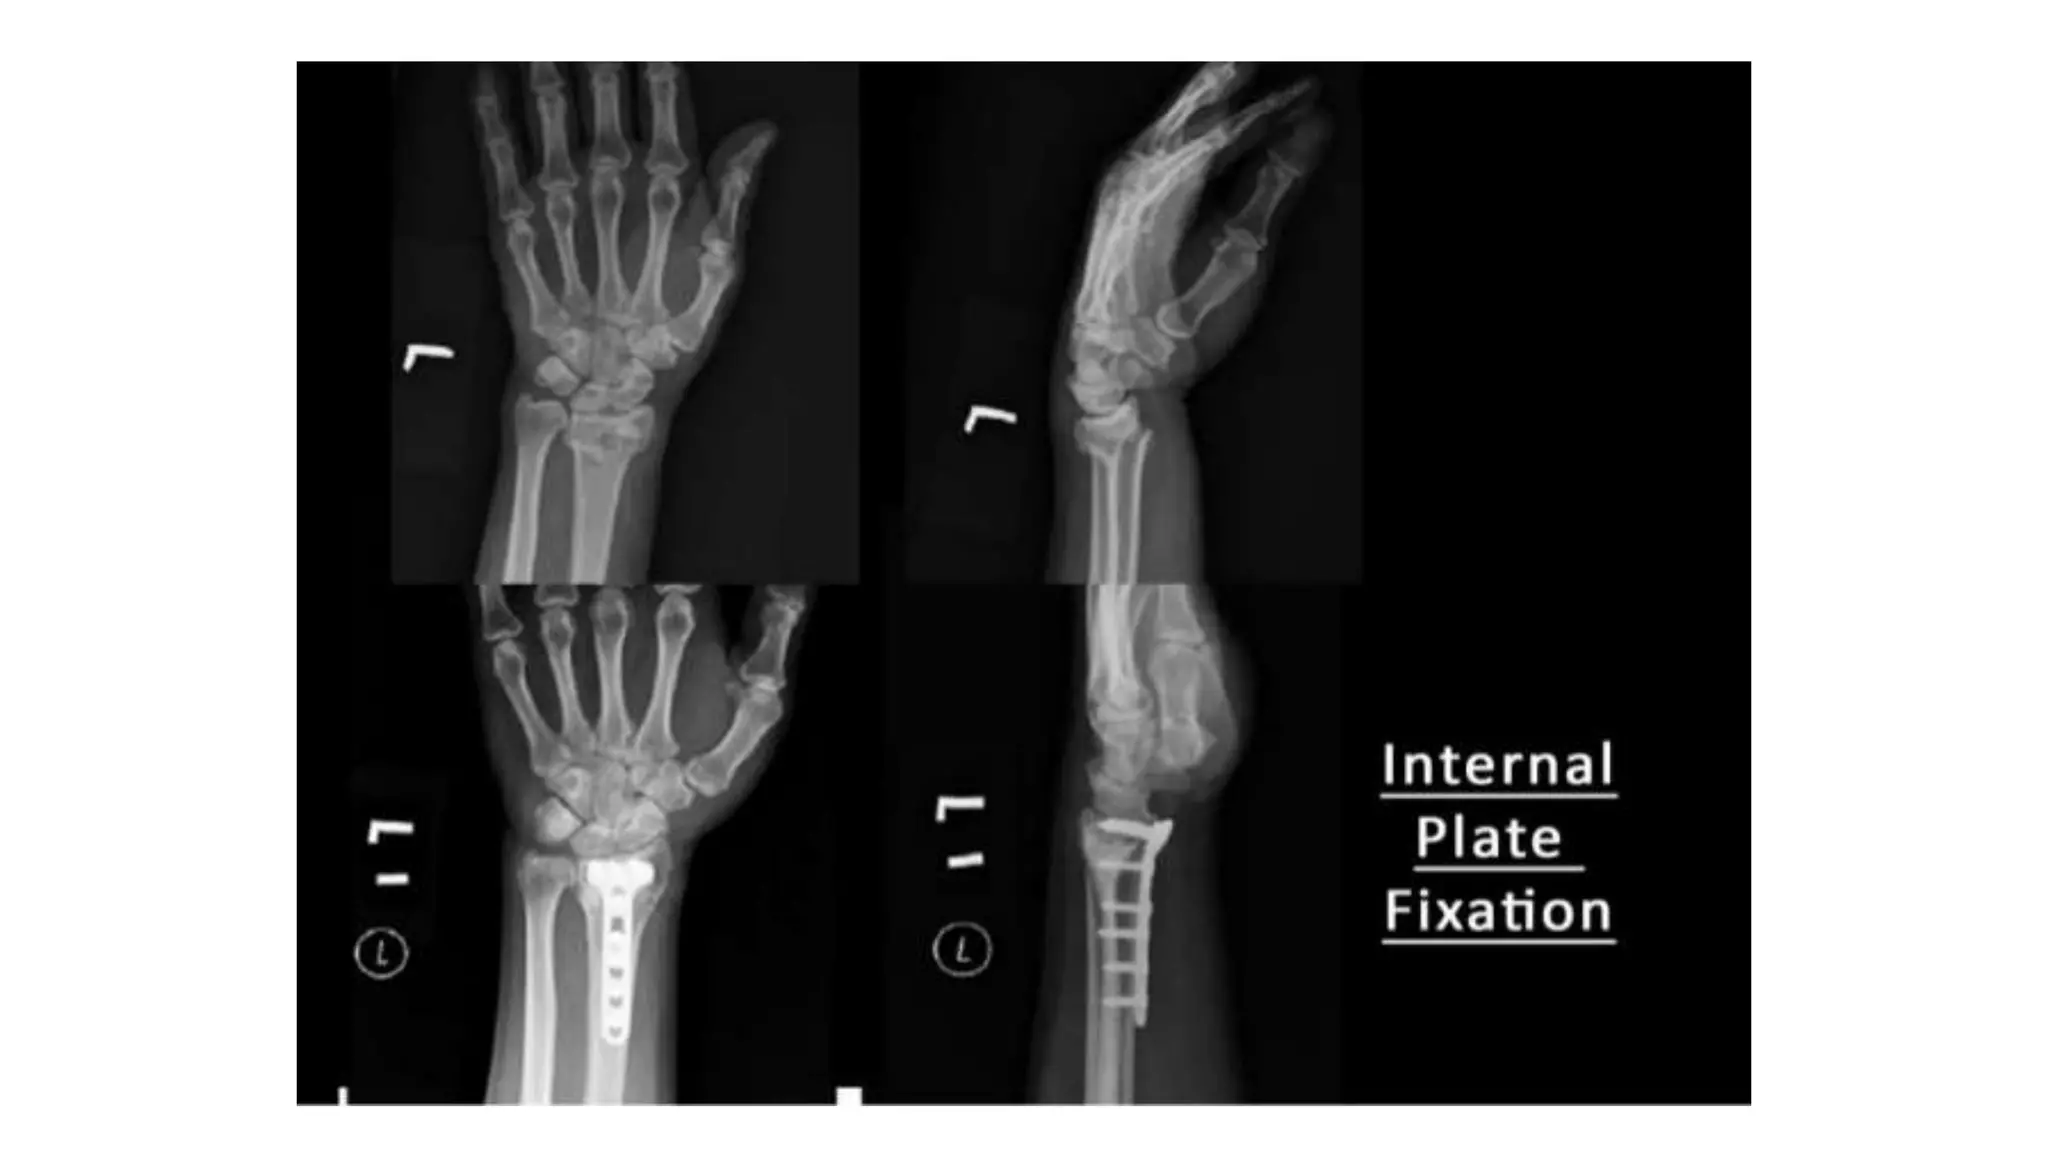

2. Surgery :

- All fragments must be

reduced into a good

position & held in a stable

manner.

- Volar locking plate are

particularly useful.